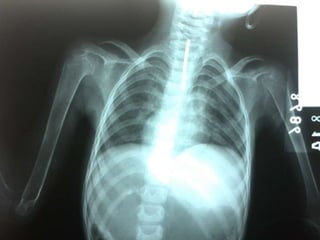

 2ndo semestre: Tórax

 Hendidura De Harrison (El diafragma

tira de las costillas ablandadas durante

la inspiración)

Manifestaciones Clínicas 1er semestre: En el cráneo  2ndo semestre: Tórax  3er semestre: Miembros inferiores y dentición.

 Rosario Raquítico  Ensanchamiento de las placas del crecimiento (hipertrofia de los tobillos y muñecas)  Hendidura De Harrison (El diafragma tira de las costillas ablandadas durante la inspiración)